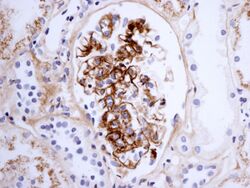

Immunostaining showing IgA in the glomerulus of a patient with Henoch–Schönlein nephritis

The diagnosis is based on the combination of the symptoms, as very few other diseases cause the same symptoms together. Blood tests may show elevated creatinine and urea levels (in kidney involvement), raised IgA levels (in about 50%[12]), and raised C-reactive protein (CRP) or erythrocyte sedimentation rate (ESR) results; none are specific for Henoch–Schönlein purpura. The platelet count may be raised, and distinguishes it from diseases where low platelets are the cause of the purpura, such as idiopathic thrombocytopenic purpura and thrombotic thrombocytopenic purpura.[5]

If there is doubt about the cause of the skin lesions, a biopsy of the skin may be performed to distinguish the purpura from other diseases that cause it, such as vasculitis due to cryoglobulinemia; on microscopy, the appearances are of a hypersensitivity vasculitis, and immunofluorescence demonstrates IgA and C3 (a protein of the complement system) in the blood vessel wall.[5] However, overall serum complement levels are normal.

Biopsy of the kidney may be performed both to establish the diagnosis or to assess the severity of already suspected kidney disease. The main findings on kidney biopsy are increased cells and Ig deposition in the mesangium (part of the glomerulus, where blood is filtered), white blood cells, and the development of crescents. The changes are indistinguishable from those observed in IgA nephropathy.[12]